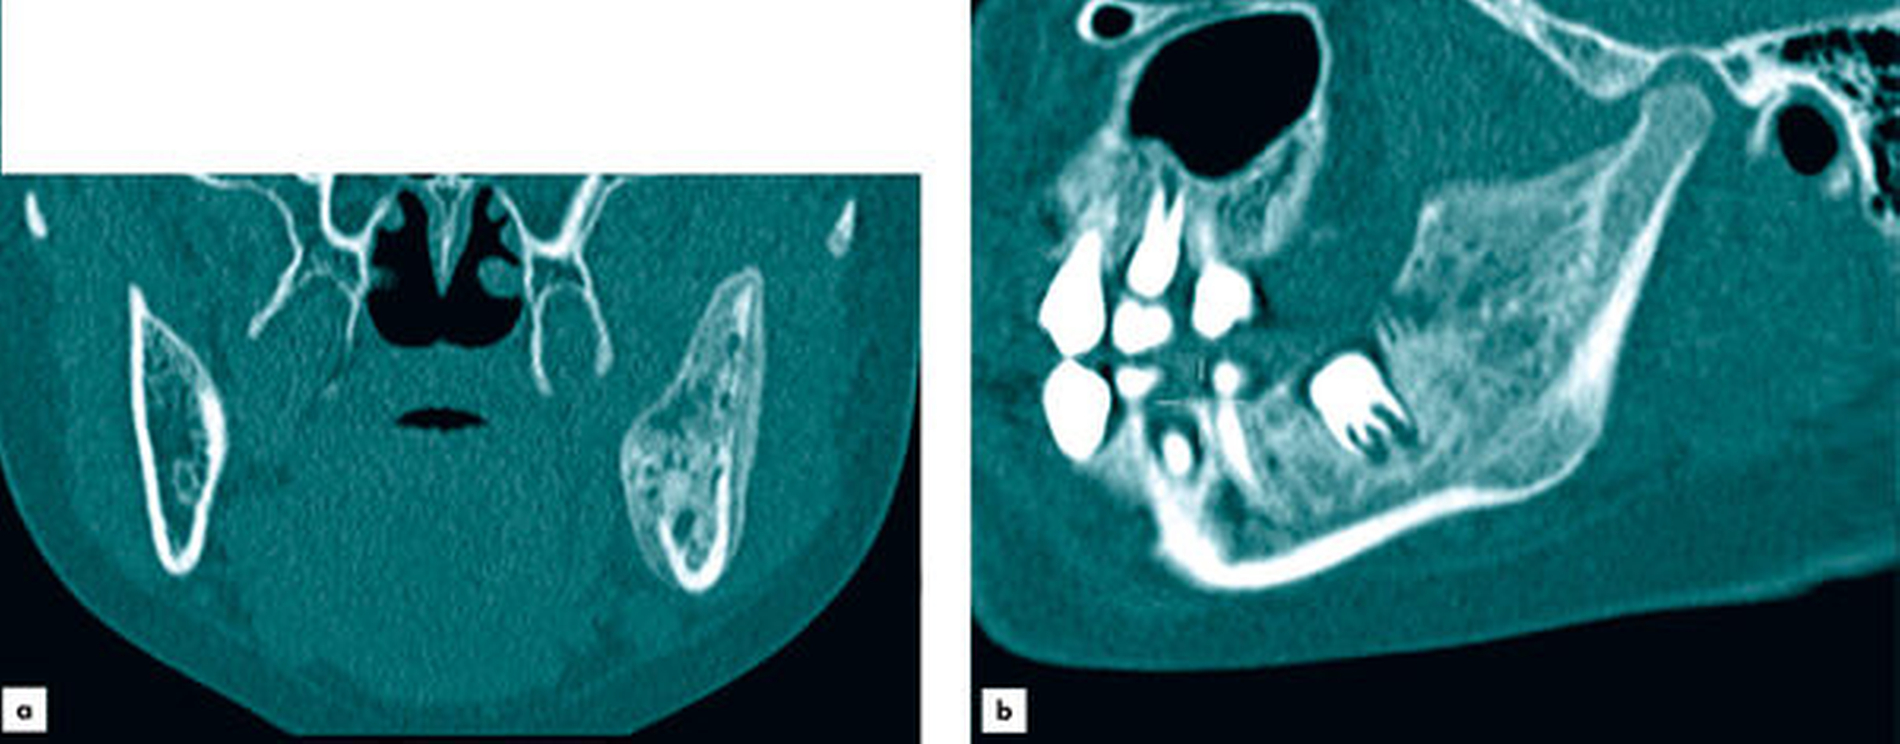

Zur (differenzial-)diagnostischen Beurteilung und Darstellung der Befundausdehnung wurde zunächst unter Berücksichtigung des Kindesalters eine Bildgebung mittels Magnetresonanztomografie (MRT) durchgeführt. Diese zeigte in der T1-Wichtung im Bereich des linken Kieferwinkels lokalisierte diffuse, inhomogene und signalarme Strukturen mit expansiver Auftreibung der Kortikalis und entzündlicher Begleitreaktion der angrenzenden Muskulatur (Abbildung 1). Aufgrund der MRT-morphologisch nicht zweifelsfrei wegweisenden Befunde erfolgte zur genaueren Beurteilung des knöchernen Gesichtsschädels eine ergänzende Computertomografie (CT), die kongruent zu den signalarmen Bereichen in der MRT milchglasartige Volumenvermehrungen des linken Kieferwinkels mit Ausbreitung in den Processus coronoideus und ins angrenzende Collum mandibulae aufwies (Abbildung 2). Die durchgeführte CT stützte bei den oben genannten, charakteristischen Kriterien (Abbildung 3) im Kontext der klinischen Befunde die Arbeitsdiagnose der fibrösen Dysplasie.

Neben der klinischen Untersuchung ist die Diagnose der fibrösen Dysplasie überwiegend radiologisch zu stellen [Vogelsang et al., 1978]. Typischerweise zeigt eine fibröse Dysplasie bildmorphologisch in Orthopantomogramm (OPTG) und CT neben einer ausgedünnten, intakten Kompakta eine charakteristische, milchglasartige Struktur der betroffenen Knochen [Fitzpatrick et al., 2004]. Abhängig davon, ob fibröse oder ossäre Gewebeanteile überwiegen, dominieren Aufhellungen oder Verschattungen die oben genannten bildgebenden Verfahren. Insbesondere zur besseren Differenzierung, respektive Abgrenzung mon- und polyostotischer Krankheitsbilder ist in ausgewählten Fällen auch eine nuklearmedizinische Skelettszintigrafie wegweisend [Vogelsang et al., 1978]. Neben klar kennzeichnenden radiologischen Merkmalen kann auch der Nachweis einer GNAS-Genmutation die herkömmliche chirurgische Biopsiediagnostik, deren Notwendigkeit immer in Abhängigkeit des zu erwartenden diagnostischen Nutzens und des individuell bestehenden Frakturrisikos evaluiert werden sollte, ergänzen [Ostertag und Glombitza, 2018].